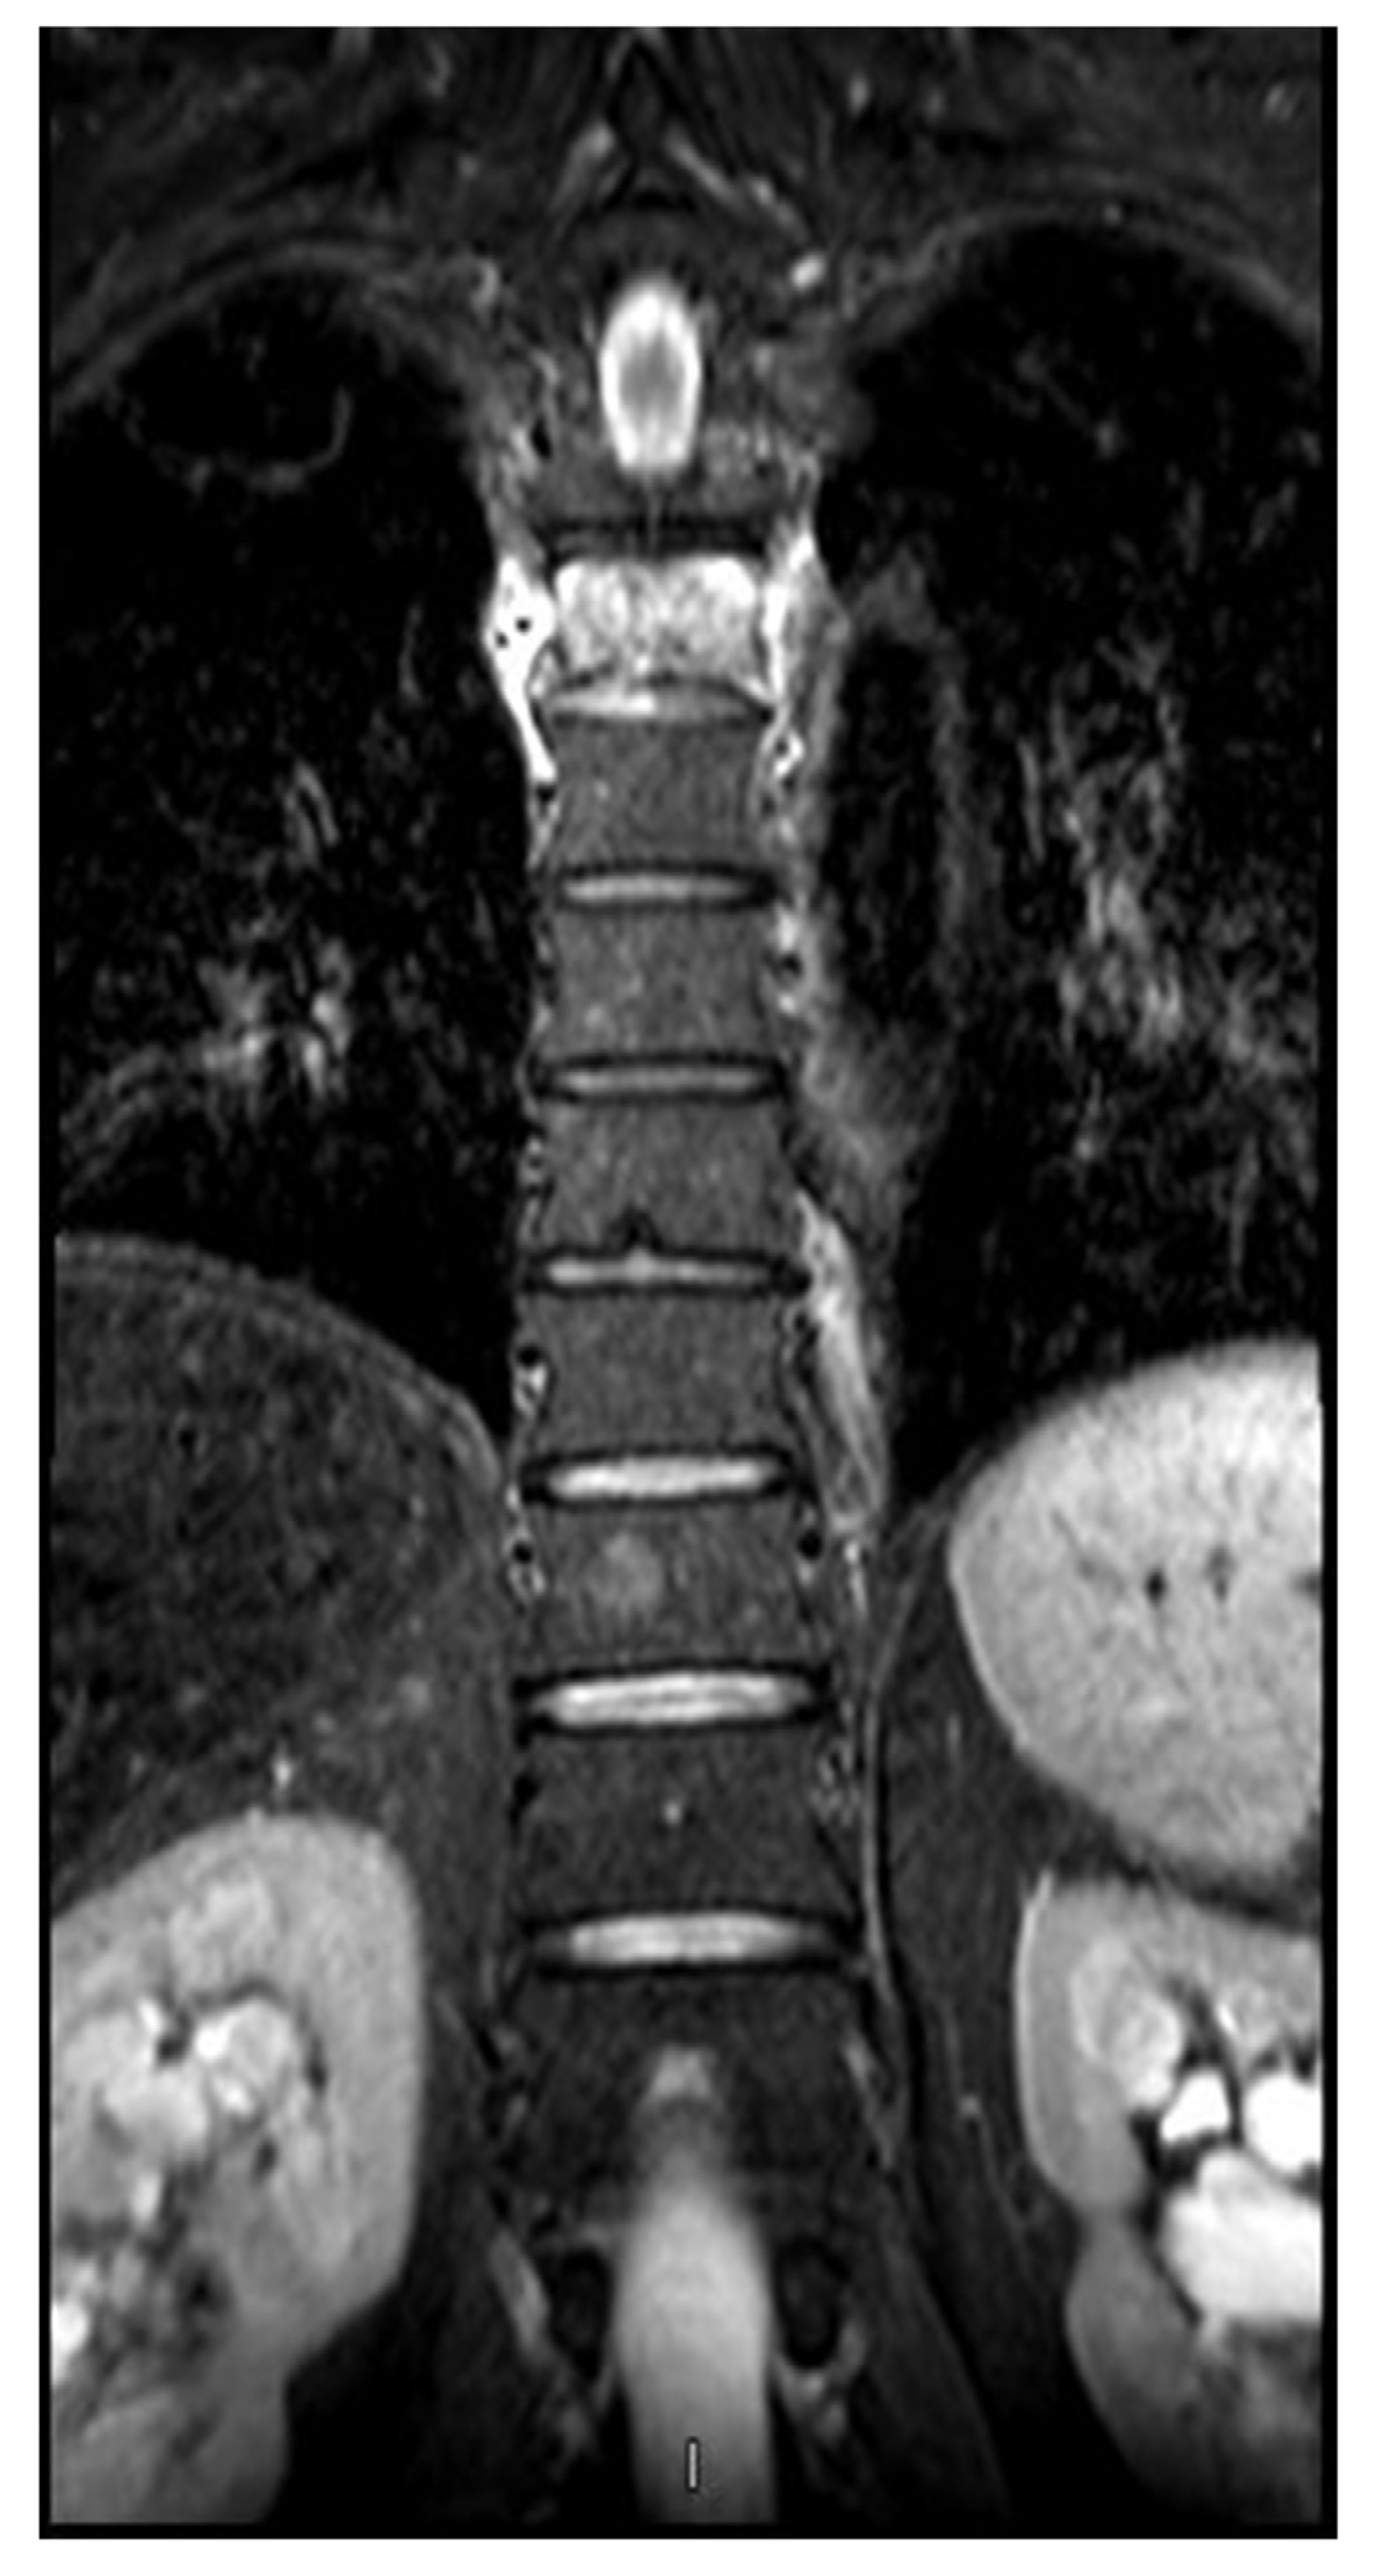

Pathologic fracture of the thoracic spine in a male master ultra-marathoner due to the combination of a vertebral hemangioma and osteopenia

2. Case presentation